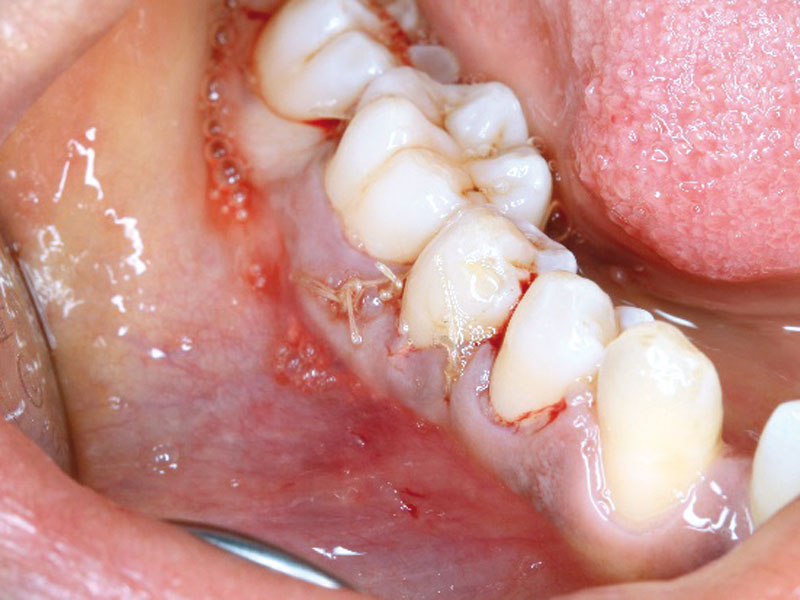

05/08 - Healing at 6 weeks post-operationRegeneration at LR6 with cerabone® and collprotect® membrane using simple papilla preservation technique - Dr. D. Chatzopoulou